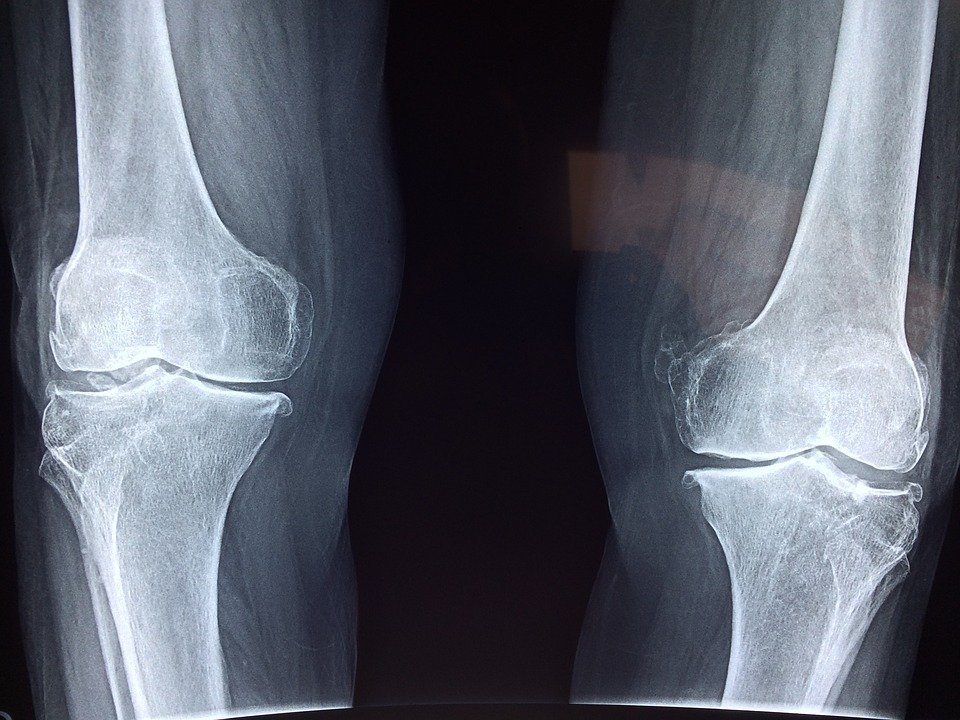

Despite the incredible regenerative capacity of our bone tissue, like everything else it has some limits. There are instances in which because of fractures, blast injuries, infections or resection of bone tumors we have very large bone defects that cannot heal spontaneously and require bone grafting surgeries. This number is increasing but right now we stand at about 2 million procedures every year (Keating, Simpson, and Robinson 2005), so it’s not a small problem. Ideally surgeons could use autologous bone from the patient as a scaffold to support the regeneration of the defect. This approach does not require donors and there is no risk of rejection, however, only limited amount of bone tissue can be used and there is the issue of having to damage a healthy bone. This is the reason why so much effort is dedicated towards finding alternatives. We became pretty good at using hydroxyapatite and other calcium phosphate minerals as a scaffold since they mimic the inorganic component of bone itself (Spadaro, Becker, and Bachman 1970). These mineral scaffolds are conducive of bone growth, this means that if we implant such scaffold, osteoblasts could eventually migrate into it and deposit bone extracellular matrix. But, these materials are not “osteoinducive” which means that they don’t attract and induce differentiation of stem cells towards osteoblastic phenotype. BMP-2 is an osteoinducive molecule that delivered with calcium phosphate scaffolds can work its magic, at least in an ideal world where side-effects do not exist. But they do induce bone growth.

Especially when used in spinal fusion surgeries, BMP-2 can have several side-effects, the worst one is probably ectopic bone formation that is caused by the leakage of BMP-2 outside the implant (James et al. 2016) . BMP-2 not only direct the differentiation of stem cells, but it can also change the phenotype of cells like myoblasts (Chen et al. 1998), adipocytes (Fraser et al. 2006) and fibroblasts (Ishihara, Weisbrode, and Bertone 2015) that inhabit the surrounding tissues, causing some problems. You don’t have to trust me on that, few years after the approval of BMP-2, the FDA issued a warning, urging clinicians to be careful with the use of BMP-2 because it was found that from 20 to 70% of the surgeries that used BMP-2 showed some sort of BMP-2-associated complications (Carragee, Hurwitz, and Weiner 2011). This data is often overlooked in scientific publications.